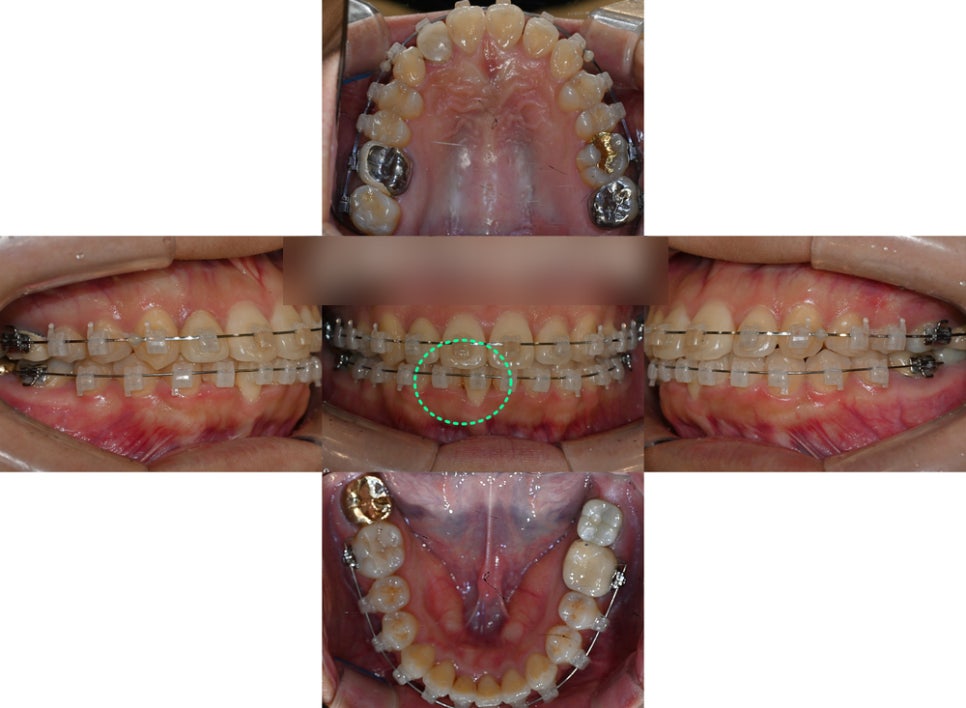

『2. 비발치 치료 과정』

앞서 계획을 세웠던대로

비발치 교정을 진행했습니다.

뻐드러져 나온 앞니 하나를

제위치 시키기 위해 전체 치아에

브라켓을 부착하여 이동을 이끌었습니다.

공간을 확보한 뒤 올바른 곳으로

움직이기 위해 교정력을 주었으며,

점차 자리를 찾아가는 아래 앞니를

확인할 수 있었는데요.

너무 과도하게 빠른 이동은

추후 치아 뿌리에 좋지 않은 영향을

끼칠 수 있기 때문에 부작용이

생기지 않도록 안전하게 도와드렸습니다.

『다행히 협조를 너무 잘 해주신 덕에

1년도 채 되지 않아

과정을 마칠 수 있었는데요.』

고민이였던 삐뚠 치열이 고르게 바뀌어

훨씬 심미적인 모습으로 바뀌었더라고요~